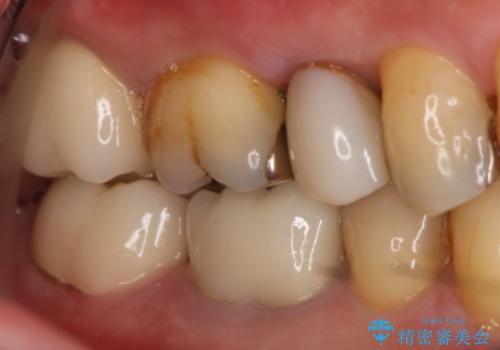

奥歯が痛む オールセラミッククラウン

- 咬んだ時に右下奥歯に痛みがあるとの事で来院された患者様です。

歯の神経は壊死していたため、精密根管治療と補綴治療を計画しました。

セラミックでの治療を希望されたので補綴はオールセラミッククラウンでの治療を選択しました。

痛みは完全に取り除かれ、咬合時の違和感もなく経過は良好です。